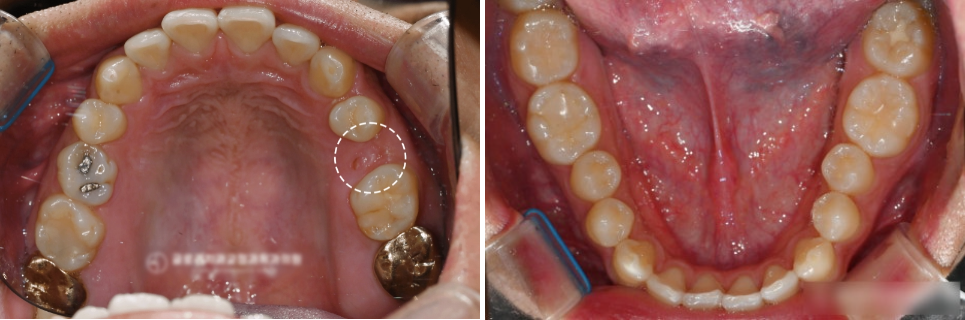

내원 당시 사진

당시, 위쪽 어금니 하나를

일찍 상실하여 임플란트 식립 예정인

상황이라는 점입니다.

그러나 이 상태가 꽤 오랜기간

방치가 되었는지 앞 어금니가 이동되면서

발치 공간이 줄어든 상태였습니다.

임플란트 보철물이 들어갈 수 있도록

공간확보가 필요했는데,